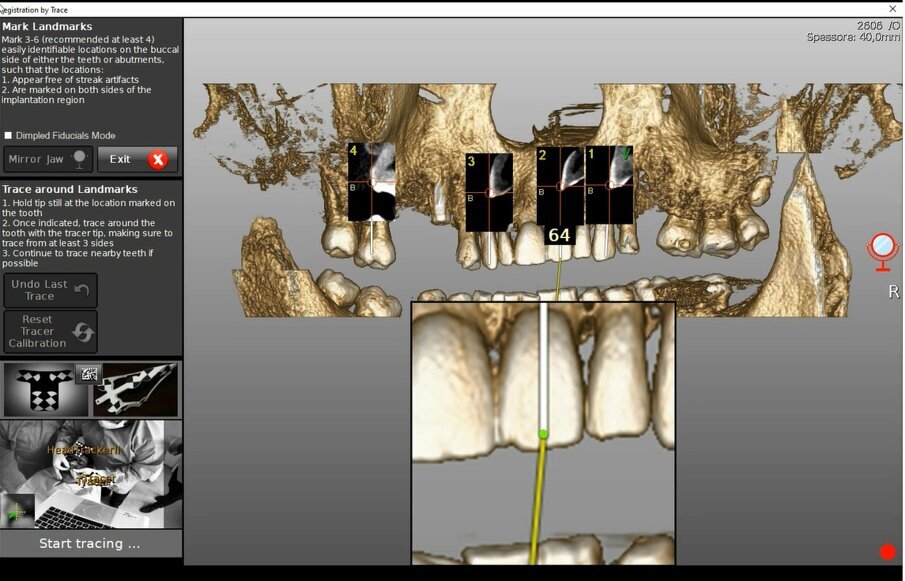

La registrazione (matching) è sempre necessaria, sia nella chirurgia guidata sia in quella navigata ma le differenze tra le due tecnologie sono già ravvisabili nell’uso che fanno di questo complesso algoritmo matematico. Nella chirurgia guidata la registrazione avviene su una media delle superfici TAC e STL del modello ed ha il compito di posizionare il modello (digitale o digitalizzato) rispetto alla TAC e, dunque, rispetto al piano di trattamento: l’errore di questo posizionamento corrisponde ad un dislocamento complessivo degli impianti durante la realizzazione clinica. Un processo protocollato, meccanizzato ed automatizzato permetterebbe di misurare questo errore e prevederlo per ciascun caso. È esperienza diffusa di ogni odontoiatra, però, che la realtà clinica, sebbene digitalizzata e protocollata, non è automatizzata; questa esperienza esita nella produzione di dispositivi la cui validità clinica non è costante ma rientra in un range che prevede, purtroppo, anche l’inaccettabilità. Nel caso della chirurgia guidata purtroppo vengono a coincidere due fattori concettualmente deleteri: l’impossibilità di verificare l’accettabilità del manufatto se non ad intervento ultimato e l’assoluta impossibilità di ripetizione della procedura chirurgica perché il fallimento spesso si associa a perdita di osso. Ciò si verifica anche in un protocollo full digital sebbene con minore frequenza e dipende dalle condizioni di lavoro assolutamente non standardizzabili. Una dima può nascondere un errore non clinicamente valutabile ma significativo. La chirurgia navigata fa uso allo stesso modo della registrazione ma esclusivamente a scopo diagnostico ed in fase di pianificazione (Figg. 3a, 3b). A scopo interventistico la chirurgia navigata richiede un’altra registrazione che si verifica in tempo reale e che ha lo scopo di posizionare i dati TAC nella realtà clinica di intervento integrandoli in un sistema di realtà aumentata on-demand (Fig. 4). Per ottenere questa sovrapposizione in tempo reale è necessaria una superficie di riferimento comune tra TAC e realtà clinica. Unica sul mercato la tecnologia navigata Navident® by Claronav® mette a disposizione ben 5 protocolli diversi per ottenere questo risultato coprendo tutto l’ampio ventaglio di realtà cliniche che ci si può ritrovare ad affrontare (pazienti totalmente edentuli, pazienti parzialmente edentuli, pazienti parzialmente edentuli ma con importanti fenomeni di scattering e beam hardening, etc.) (Figg. 5a-5f).

Nel protocollo Trace&Place, che presentiamo con questo caso, la superficie di registrazione a scopo interventistico sono i denti. La superficie dei denti viene letta in tempo reale mediante una scansione per tastatura attraverso un dispositivo apposito standardizzato nel sistema: Il Tracer Tool®; perché il sistema possa procedere a questa scansione è necessario anzitutto informarlo della posizione della punta del tastatore mediante una manovra di calibrazione. Si scelgono quindi tre o più denti dal modello 3D ricavati dai dati TAC del paziente indicando un preciso punto facilmente identificabile da cui iniziare la scansione (ad esempio la punta di una cuspide o una particolarità anatomica unica come una fossetta di usura). Se ne tastano le superfici con movimenti rapidi per lo più di traslazione dello strumento; un feedback sonoro segnala l’inizio, dall’esecuzione e dal termine di ogni scansione. La scelta dei denti non può essere causale: essi devono essere sufficientemente distanti e distribuiti nell’arcata per rappresentare un solido abbastanza descrittivo della regione clinica da approcciare. Ciò è quanto veniva effettuato nel caso in questione (Figg. 6a-6d).

Figg. 6a-6d - Tracciatura della superficie di riferimento in tempo reale. a) Calibrazione del tastatore; b) Selezione dei denti e dei punti di partenza della scansione per tastatura; c) Fasi di scansione (tracer registration); d) Dettaglio clinico della procedura di tracer registration.